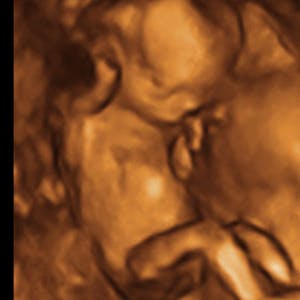

Gravid

Vi gør en dyd ud af at klæde dig godt på både før, under og efter din graviditet. Vi ved, at der kan komme mange spørgsmål til din graviditet, fødsel, amning, din babys udvikling og mange flere emner, derfor har vi samlet guides, tips & tricks samt læsernes egne fortællinger i dette gravid univers.